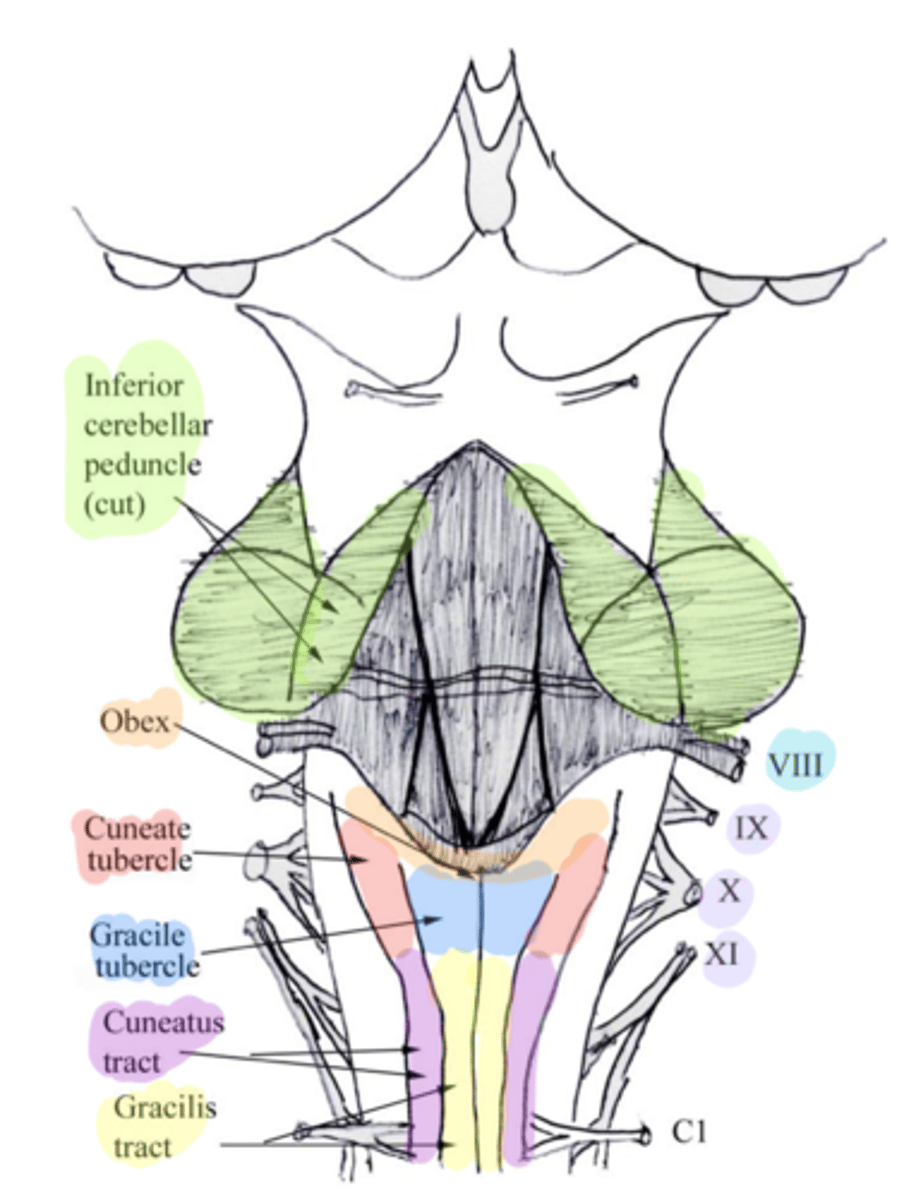

white matter stalks that connect the medulla to the cerebellum

**these help to form the lateral walls of the caudal portion of the 4th ventricle

inferior cerebellar peduncles

medial paired ridges of tissue on the dorsal aspect of the closed portion of the medulla

tractus gracilis

lateral paired ridges of tissue on the dorsal aspect of the closed portion of the medulla

tractus cuneatus

superior ends of the medial paired ridges of tissue on the dorsal aspect of the closed portion of the medulla, formed by namesake nuclei

gracilis tubercles

superior ends of the lateral paired ridges of tissue on the dorsal aspect of the closed portion of the medulla, formed by namesake nuclei

cuneatus tubercles

V-shaped boundary of the caudal aspect of the 4th ventricle that marks the boundary between the open and closed portions of the medulla

obex

name the groove

pontomedullary junction

general portion of the medulla

open medulla

general portion of the medulla

closed medulla

pyramids

ventral median fissure

pyramidal decussation

C

inferior cerebellar peduncles

cuneate tubercle

gracilis tubercle

cuneatus tract

gracilis tract

obex